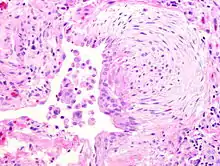

![]() | Lymphocyte | Micrograph showing lymphocytes in caseating granuloma. | Category: Lymphocytes | Lymphocyte |